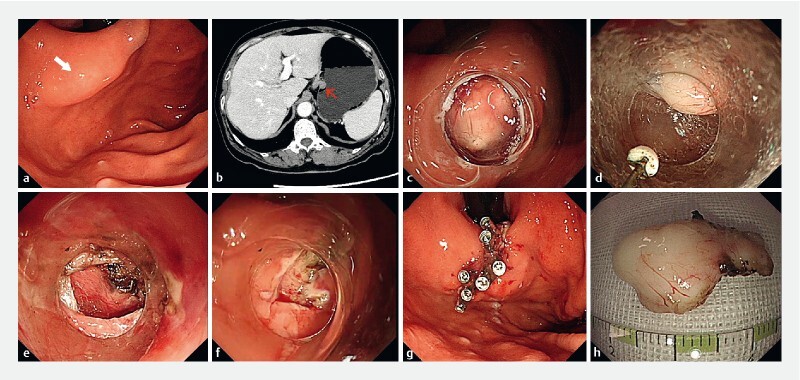

A 60-year-old woman with a submucosal tumor originating from the muscularis propria located in the gastric fornix ( Fig. 1 a ) was referred to our hospital. Contrast-enhanced computed tomography (CT) showed a well-defined and low-density mass close to the cardia ( Fig. 1 b ). Owing to its hard-to-reach location, we decided to perform an optimized gastric endoscopic full-thickness resection (EFTR). This method preserved all the residual mucosa to achieve tension-free closure. After a submucosal saline injection, a 1.5-cm incision was made at the edge of the lesion ( Fig. 1 c ). In the current method, we performed a submucosal dissection to simultaneously create a tunnel ( Fig. 2 , Video 1 ). Direct advancement of the endoscope into the fundus tunnel was performed, and the lesion was completely retrieved without removing any of the mucosal layers ( Fig. 1 d ). A full-thickness defect was exposed after removing the mass through the tunnel ( Fig. 1 e ). Subsequently, two edges of the remaining mucosa were easily clipped together ( Fig. 1 f, g ). The total wound closure time closure was 6 minutes. The submucosal tumor measured 25 mm at the highest diameter externally ( Fig. 1 h ). Postoperatively, the patient remained asymptomatic and was discharged on the third day without any complications.

A submucosal tumor in the gastric fornix. b Computed tomography scan showing a well-defined tumor near the cardia. c The tumor visualized after a 1.5-cm incision was made along the border. d Endoscopic tumor resection in which the tumor was removed through the tunnel. e The exposed full-thickness defect. f The remaining mucosa after gastric full-thickness resection. g Endoscopic view after closure. h External view of the final resected specimen.